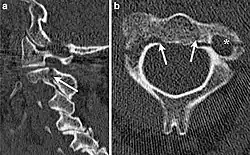

Hangman's fracture

| CT scan of hangman's fracture | |

Hangman's fracture is the colloquial name given to a fracture of both pedicles, or partes interarticulares, of the axis vertebra (C2).[1]

Although a hangman's fracture is unstable, survival from this fracture is relatively common, as the fracture itself tends to expand the spinal canal at the C2 level. It is not unusual for patients to walk in for treatment and have such a fracture discovered on X-rays. Only if the force of the injury is severe enough that the vertebral body of C2 is severely subluxed from C3 does the spinal cord become crushed, usually between the vertebral body of C3 and the posterior elements of C1 and C2.